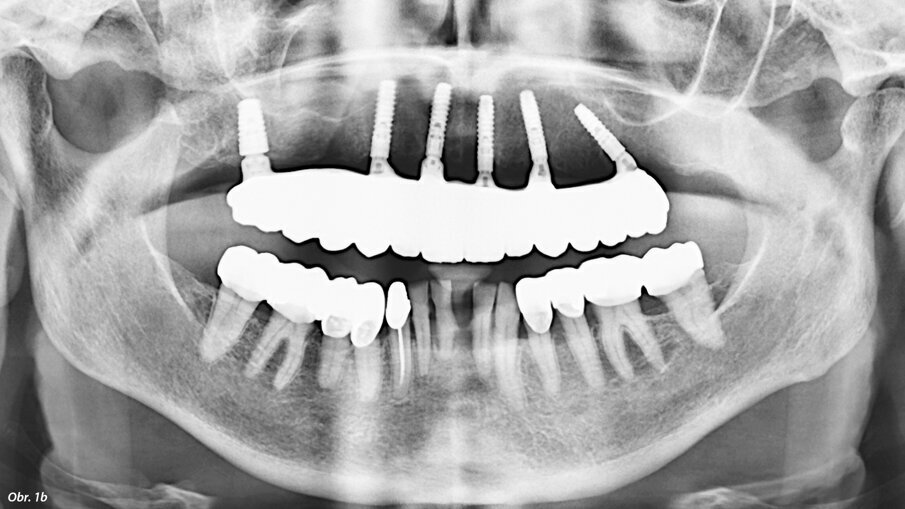

V dnešní době stále více implantujeme v místech s nedostatkem kosti pro klasickou implantaci. Nedostatek nabídky kosti často řešíme pomocí augmentačních postupů, stále častěji s využitím buněčné terapie – například kombinací augmentátů s destičkovými koncentráty (PRF, PRGF, PRP). Stále oblíbenějším řešením je využití stávající kosti pomocí skloněných implantátů. S meziodistálně skloněnými implantáty se lze často vyhnout problematickým strukturám, jako je foramen mentale nebo čelistní dutina, např. v rámci konceptu „all on four“. Často opomíjená možnost je vestibuloorální sklon implantátu. U pacientů s vhodnou anatomií čelisti můžeme tímto způsobem výrazně zjednodušit a zkrátit dobu terapie. Nejčastěji uplatňovaným postupem v horní čelisti je využití silné stěny čelistní dutiny pro zavedení implantátu, popřípadě navigace do neobvyklých kostěných struktur, které mohou vzniknout například kostním zhojením periapikálního granulomu. V dolní čelisti je pak zásadním aspektem zavedení implantátu tak, abychom se vyhnuli mandibulárnímu kanálu a vyřešili tak vertikální nedostatek kosti (obr. 1a, b).

Na naše oddělení se dostavila pacientka, 52 let, s implantátem v místě 36, který byl zaveden na jiném pracovišti asi před 6 lety. Implantát vykazoval známky odhojení. Na OPG (ProMax, Planmeca) byl patrný velký úbytek kosti v okolí implantátu způsobený periimplantitidou (obr. 2). Proto byl implantát odstraněn, defekt byl exkochleován. Po 3 měsících bylo zhotovené CBCT (ProMax, Planmeca) pro plánování náhrady implantátu (obr. 3). Po zvážení všech možností (vertikální augmentace, short implant) jsme se rozhodli k zavedení tilted implantátu, který bude zaveden tak, aby míjel průběh mandibulárního kanálu (obr. 4). CBCT sken nám pomohl přesněji určit polohu mandibulárního kanálu. V programu jsem si následně vybral vhodný průměr i délku implantátu a určil jeho polohu tak, aby se vyhnul průběhu kanálu a zároveň respektoval aktuální nabídku kosti. Je velmi důležité podívat se na situaci z různých pohledů, abychom se ujistili, že jsme ošetření správně naplánovali.